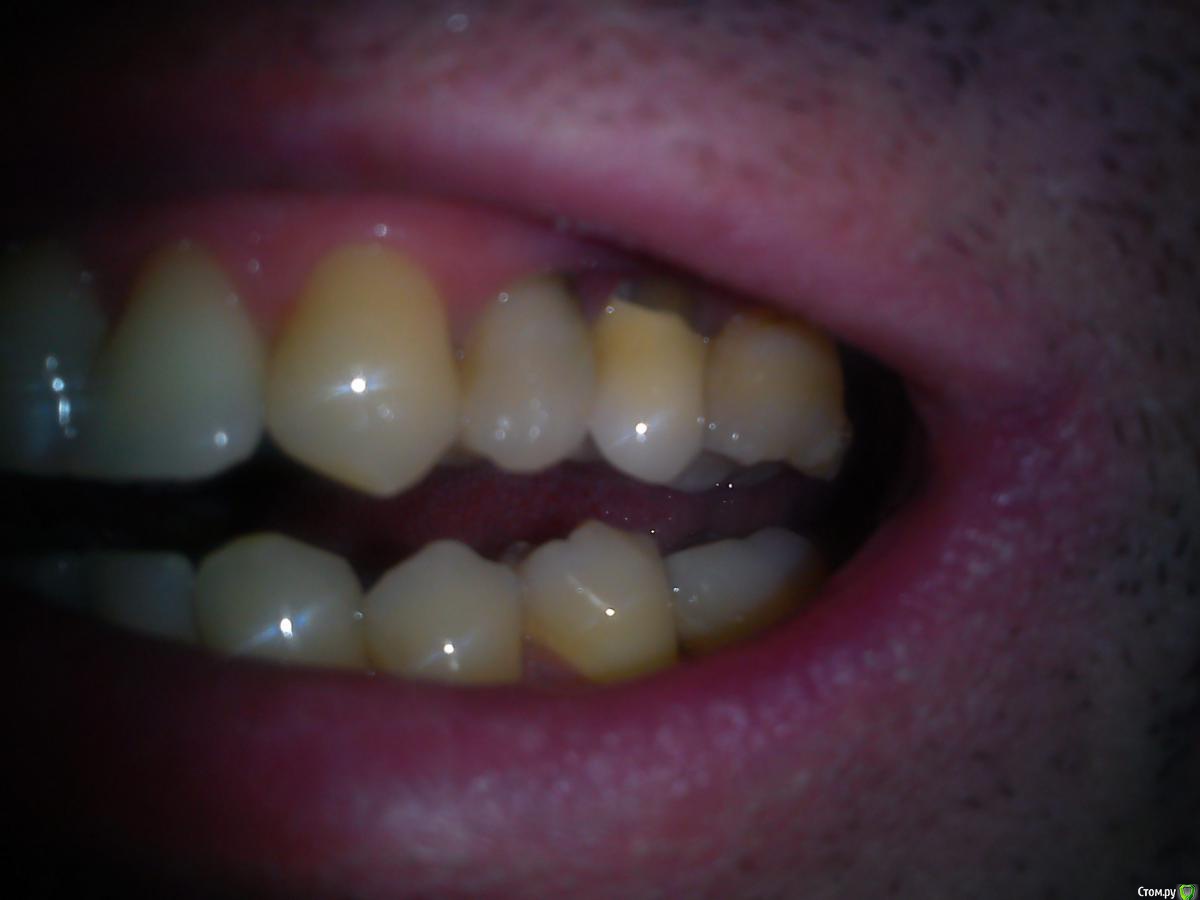

Макс111 Опубликовано 16 декабря, 2015 Поделиться Опубликовано 16 декабря, 2015 Добрый день!По возможности, прошу посмотреть мою КТ. Правда, не разобрался какую именно папку выкладывать, поэтомувот тут ссылка только на папку с файлами с расширением .DCM https://yadi.sk/d/NQrtBNRKmFtRC А вот тут на все содержимое диска вместе с программой для просмотра, на всякий случай:https://yadi.sk/d/O5yoL0QImFu3Y Так же к теме прикрепляю фото 24, 25 с внешней и внутренней стороны, а так же фото ниж ч там где 46 У меня пародонтит, и тд.В целом, вопрос по 24 и 25 зубу, между ними как видно большой карман. 25 это коронка на зубе, десна опустились и она полностью оголилась, видно уже корень , коронка на десной на пару мм. 24 это в общем то пломба огромная на весь зуб.Что можно сделать? Мне предлагают снять коронку, потом сделать лоскутную операцию, в ходе которой подсадить материал для формирования кости, чтоб уменьшить этот карман и потом сделать сделать коронку и на 25 и на 24 тоже коронку одеть.Какое ваше мнение по 24, 25? Как бы вы сделали, в какой очередности?27 и 28 потерял около 9 мес назад, над ними была киста, ее вырезали.А ну и плюс хронический гайморит. Так же прошу посмотреть в низу 46 зуб, можно ли туда вкрутить имплант или предварительно регенерировать кость нужно? каким методом?у 7 ки там такая форма, что между зубами видимо будет пустота? Как с этим бороться? Когда там был зуб так и были и поэтому 46 портился, стояла пломба, но 3 месяца назад он раскололся, сохранить возможности не было, плюс была киста и его пришлось удалить..Стоит ли сразу удалить 48, чтоб он не давил на 47 или можно подождать пока верх сделаю, чтоб было чем есть пока? Спасибо, если кто то посмотрит! Ссылка на комментарий